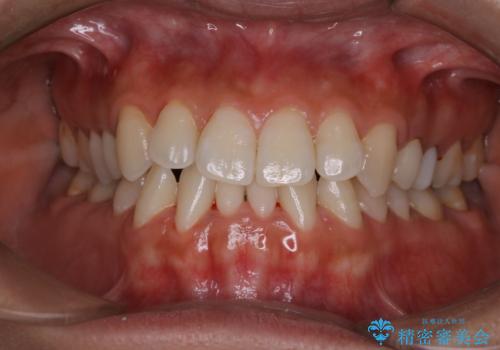

海外へ行く前にクリーニングできれいにしたい

- 長期で海外へ行くため、全体的にきれいな状態にしてほしいとのことでした。PMTC60分コースを行いました。

もっとも、効果的な治療法がPMTC(歯科医院で専門的な機械や材料を使用してクリーニング)を定期的に行うことです。